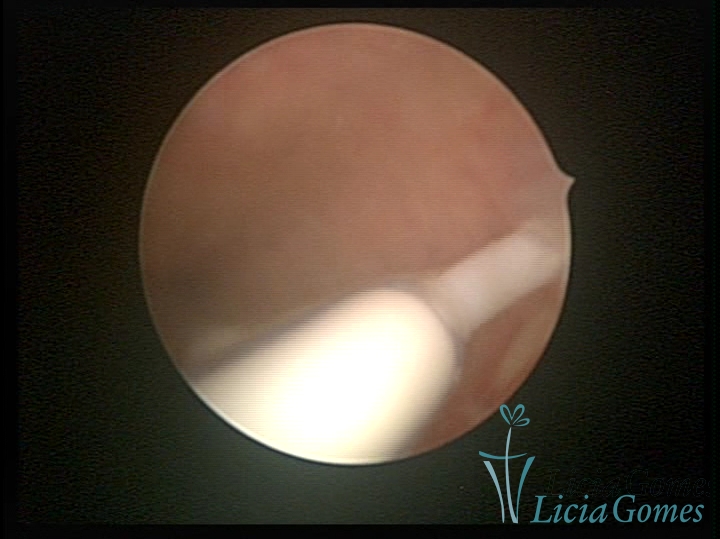

Canal cervical com fio do DIU